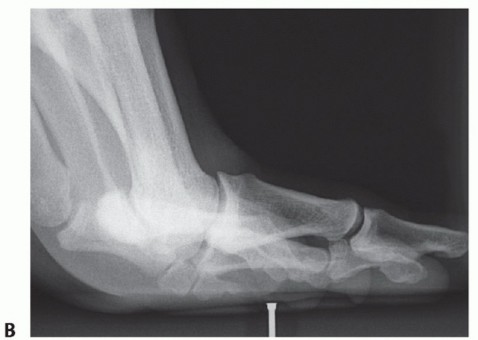

A thorough radiographic evaluation is mandatory (including weight-bearing views of the foot in the

anteroposterior [AP], lateral, and oblique planes) (FIG 3). Sesamoid axial views may also be helpful. Bilateral standing AP views are mandatory for comparison. Sesamoid station is assessed.

Forced (stress) dorsiflexion lateral views are helpful to diagnose disruption/diastasis of a bipartite sesamoid or a sesamoid fracture (FIG 4). It will also suggest a complete distal disruption of the FHB if the sesamoid(s) fails to migrate distally with dorsiflexion of the hallux. Studies suggest that more than 10.4 mm from the tip of the tibial sesamoid to the phalanx or more than 13.3 mm from the fibular sesamoid equates to a 99.7% chance for

plantar complex rupture.11 Compare the injured to uninjured side.

FIG 4 • Dorsiflexion stress lateral radiographs. A. Normal. Note the position of the sesamoids. B. Abnormal. Note the proximal migration of the sesamoid complex.